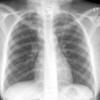

Normal PA

24 yo male

Date: 06/08/2016

Views: 6331